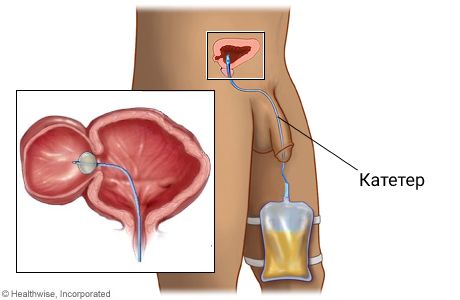

Если дивертикул выявлен на фоне обструкции выходного отверстия мочевого пузыря, то в первую очередь нужно устранить её. Для этого выполняют катетеризацию мочевого пузыря и медикаментозное лечение доброкачественной гиперплазии предстательной железы. Этот подход позволяет уменьшить послеоперационные осложнения и риск повторных операций.

Катетеризация мочевого пузыря

Чтобы предотвратить инфекционно-воспалительные осложнения, после операции проводится катетеризация мочевого пузыря и антибактериальная терапия [14][35]. Также в послеоперационном периоде необходимо обильное питьё для естественного промывания мочевого пузыря. На следующий день после хирургического вмешательства нужно начинать вставать и ходить, но после полостной операции следует избегать чрезмерных нагрузок в течение нескольких месяцев.